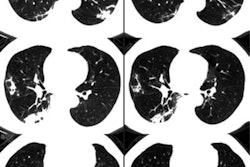

Updates on the novel coronavirus disease (COVID-19) have dominated the healthcare news circuit since early reports of the outbreak emerged in January this year, and CT has been a central figure all throughout.

Indeed, initial studies have shown CT to be vital for the early diagnosis of COVID-19 and in tracing disease progression. Researchers from the U.S. and China laid out several of the most notable CT findings that appear in individuals with COVID-19 as a reference for radiologists tasked with detecting the disease. And a separate group showed how CT and x-ray helped confirm the first case of COVID-19 in the U.S.

Recent research has also revealed the capacity of CT to uncover COVID-19 in cases in which initial DNA tests are negative. This finding spurred the Chinese National Health Commission to make clinical diagnosis through CT an official method for confirming the disease in Wuhan -- the presumed source of the outbreak -- and surrounding towns in Hubei province.

Though somewhat overshadowed by coverage of the coronavirus, research on CT lung cancer screening certainly has made its mark recently as well. The team behind the Dutch-Belgian Randomized Lung Cancer Screening (NELSON) trial finally published its full findings in the New England Journal of Medicine. Researchers from North Carolina also demonstrated the viability of a mobile CT lung screening unit, which they used to deliver screening services to underserved and uninsured populations.